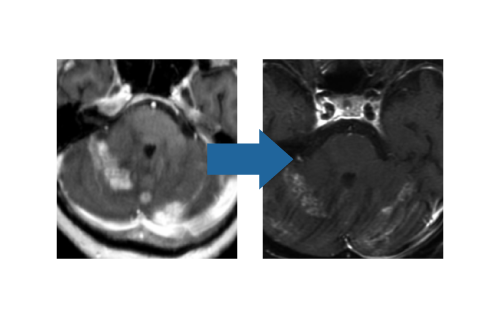

しかし、切り取るわけではないので、あくまでも治療目的はこれ以上大きくさせないこと。とはいえども、縮小し改善するケースは実際多いのです(図3)。

ガンマナイフ著効例(図3)

大方コントロール良好。しかし、術後脳浮腫の可能性は考慮する。90%近くで腫瘍の成長を止めることができ、大半が縮小傾向となります。しかし、遅れてガンマナイフによる炎症性変化として、周囲正常脳に一過性の脳浮腫(脳組織間質に水がにじむようになる)を伴うことがあります(10-20%程度)(図4)。 その際に、場所により頭痛・麻痺・てんかんなどの症状を呈することもあり、ステロイド投薬が必要となる場合があります。切らない治療と言えども決して安全とは言い切れません。患者さんの状況により、手術・全脳照射・分子標的薬剤などの選択に考慮が必要となります。

脳浮腫合併例(図4)